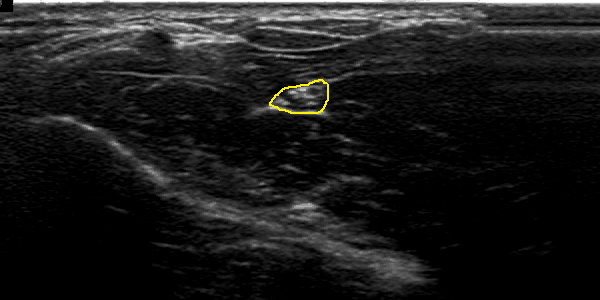

Figure 2 illustrates and example of results in two US images from two different patients. Figures 2 (b) and (e) shows the localisation obtained with CNN and spatiotemporal consistency. The nerve segmentation by PGVF is depicted in figures 2 (c) and (f). One can observe that the automatic segmentation is very close to the one obtained form human experts figures 2 (a) and (d).

Fig. 2: An example of the obtained using deep learning with spatio temporal consistency. Images show the median nerve of two different patients. Left column (a) and (d), each image is the ground truth of the median nerve of each patient. The middle column (b) and (e), represents the localisation result using CNN and spatiotemporal constraint. Right column (c) and (f), shows the segmentation result using PGVF algorithm